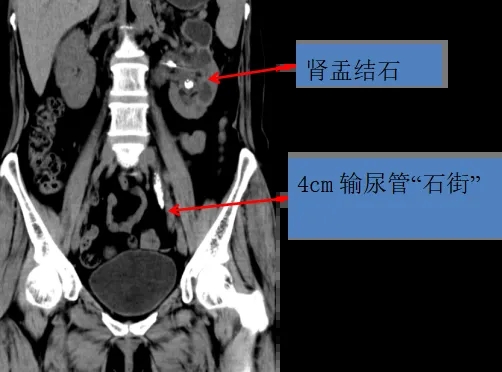

近日,陕西省中医医院泌尿外科利用输尿管镜联合微通道经皮肾镜技术,成功完成一例“双镜联合”钬激光碎石取石术,为患者一次解除了长达4cm输尿管“石街”合并肾盂结石。

患者尚某,59岁,女性,因左侧腰痛伴发热15天慕名来到陕西省中医医院泌尿外科,面对患者痛苦的表情以及殷切的期望,董海军主治医师一边缓解患者病痛,一边尽快完善检查,发现左侧输尿管中段多发结石,已经形成了长度达4cm“石街”,引起输尿管梗阻扩张,左肾多发结石、肾脏积水、积脓、肾功能不全。张旭主任医师团队讨论后制定周密治疗方案,决定先行经皮肾造瘘引流患侧肾脏积脓,积极抗感染治疗。经治疗,患者体温恢复正常,引流尿液清亮淡黄色,再次评估患者结石情况,决定手术方案为:“双镜联合”一次性解决输尿管”石街”及肾盂结石。